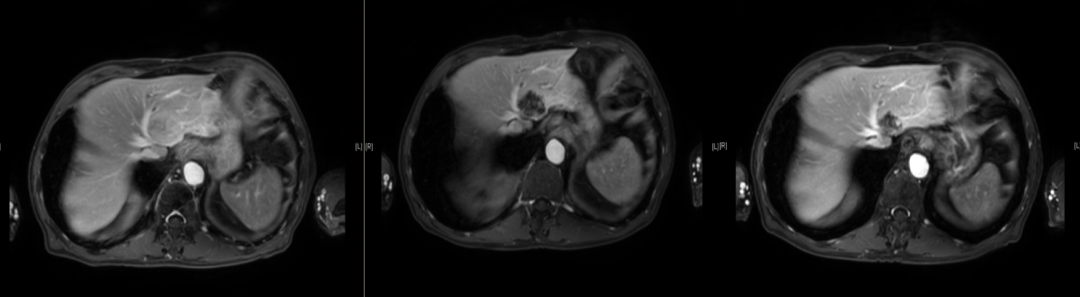

诱导化疗后疗效评估:

首诊10.28(图左)42mm*31mm;一程治疗后11.18(图中) 35mm*27mm*36mm;两个程治疗后12.12(图右):27mm*25mm*21mm

2程治疗后疗效评价:

肝左外叶实性结节,大小约30*20mm,形态呈椭圆形,内部为低回声,内部回声分布均匀。CDFI:病灶内未见明显血流信号。结合超声造影考虑Malignant(拟转移性病灶治疗后改变,病灶较化疗前检查明显缩小,超声造影显示病灶内大部分无活性,CEUS LR- Treated)。